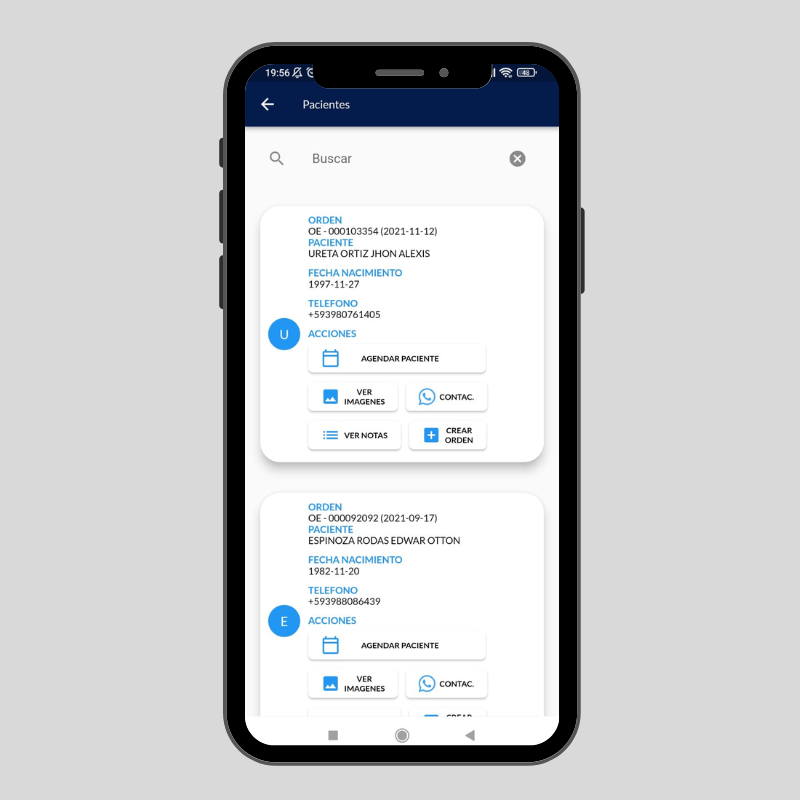

Tu tiempo es valioso imagenes, resultados y más directo a su teléfono y al de su doctor!

- Dar una atención de calidad

- Contar con personal de experiencia en cada área.